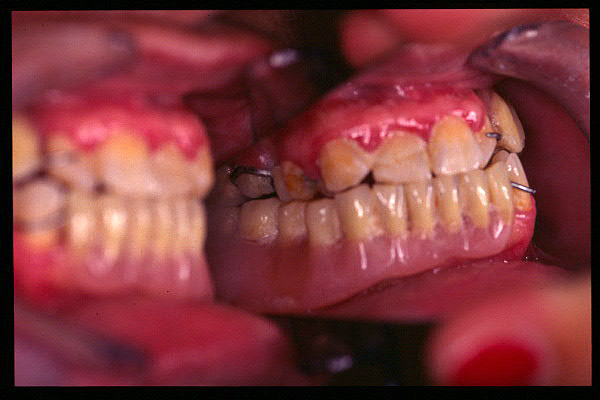

CM Caries, patología periodontal, desgaste.

CM Desgaste por bruxismo, presencia de cálculo